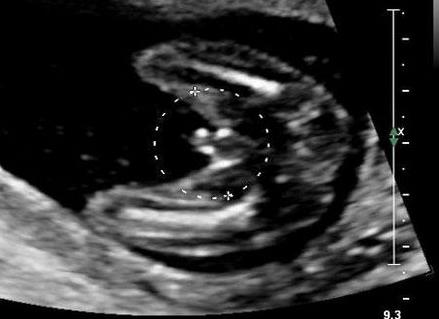

Резус-фактор — это белок, содержащийся в клетках крови у 85% людей, которых называют резус-положительными. У остальных 15% такого белка нет. Их называют резус-отрицательными. Положительный или отрицательный резус-фактор передается по наследству, но при этом есть вероятность наследования через несколько поколений. То есть, если ребенок унаследовал его, например, от бабушек, он может оказаться не таким, как у родителей. Если обе бабушки (или оба дедушки, или бабушка по линии одного родителя и дедушка по линии другого) резус-отрицательные, а оба родителя резус-положительные, то ребенок вполне может иметь отрицательный резус-фактор. И такое происходит в 25% случаев. Подробнее ...